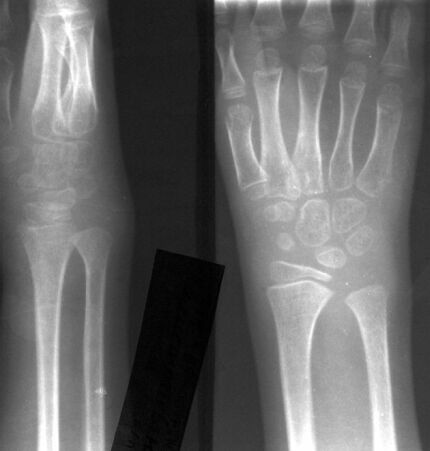

недели с диагнозом ушиб, повреждение связок правого л\запястного сустава. После чего особых жалоб по поводу травмы не предьявляла. Болевой синдром возобновился с февраля 2002 года. Травму в этом году отрицает. Обращает на себя внимание выраженная гипотрофия н\3-с\3 правого предплечья, увеличение в объёме в области л\запястного сустава и кисти в области костей запястья, формирующаяся лучевая косорукость.Объём движений в л\запястном суставе резко ограничен из-за выраженной болезненности при движении. Пальпация л\запястного сустава умеренно болезнена. В покое болей нет, ночных болей нет. Движения в пальцах кисти в полном объёме, сила мышц пальцев достаточная (такая же как и слева), чувствительность в пальцах, области л\запястного сустава и предплечья не нарушена. Температура в пределах нормы, сон и аппетит не нарушены. Анализы крови и мочи не изменены. Rg-ки: остеопороз костей запястья и пястных костей, увеличение размеров костей запястья (интенсивный рост?), несколько увеличен диастаз между костями предплечья в н\3.Предполагаемый диагноз (если его так можно назвать): Посттравматические нейротрофические изменения в области н/3 правого предплечья и кисти.В прилагаемых Rg-граммах в названии указана дата исследования. 14.09.00, 26.02.02.Хотелось бы услышать ваше мнение.С уважением,Александр Е. Клоков